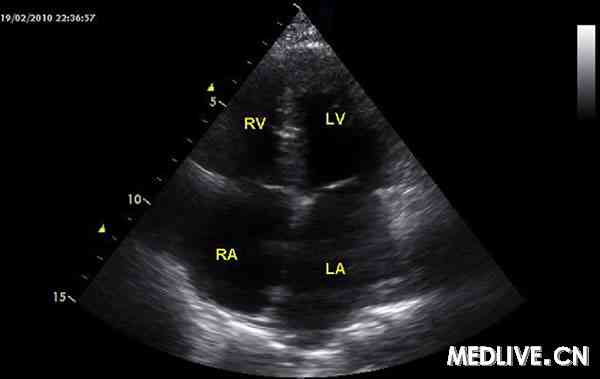

临床心脏病学检查结果正常。心电图提示Ⅰ型房室阻滞、双相P波、轴右偏和复极异常。24 h心电图显示,发生了5次无症状的心动过速">室上性心动过速,每次最多可持续15 s,发生了1次窦性心动过速。超声心动检查明确了限制性心肌病的诊断(见图1),但未发现心肌增厚。呼吸测功检查显示呼吸功能严重下降,仅为正常值的50%。

图1 超声心动检查